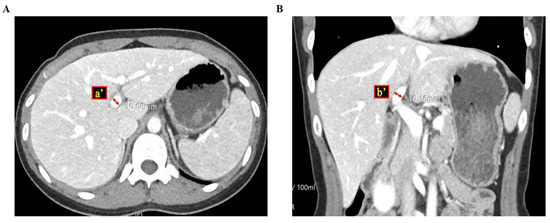

2.2. RPVA/LPVA